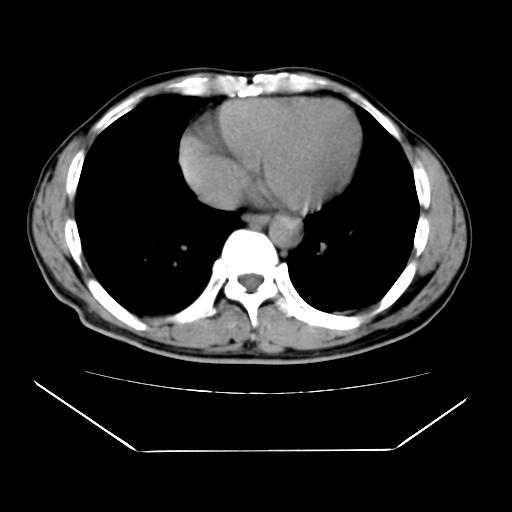

男性,55岁,外院体检afp明显升高,但b超未发现异常,否认乙肝病史。来我院ct增强。有延时扫描。

肝脏右叶动脉期可见低密度影,至延迟期被充填,考虑血管瘤可能性大。

肝右叶病灶

不排除肝右叶肝癌可能。

如果这个是癌灶的话则下腔静脉有瘤栓可能

肝6段血管瘤

血管瘤可能性大。

考虑肝右静脉影。